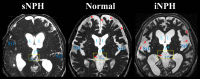

To clarify the pathogenesis of two different types of adult-onset normal-pressure hydrocephalus (NPH), we investigated cerebrospinal fluid distribution on the high-field three-dimensional MRI. The subarachnoid spaces in secondary NPH were smaller than those in the controls, whereas those in idiopathic NPH were of similar size to the controls. In idiopathic NPH, however, the basal cistern and Sylvian fissure were enlarged in concurrence with ventricular enlargement towards the z-direction, but the convexity subarachnoid space was severely diminished. In this article, we provide evidence that the key cause of the disproportionate cerebrospinal fluid distribution in idiopathic NPH is the compensatory direct CSF communication between the inferior horn of the lateral ventricles and the ambient cistern at the choroidal fissure. In contrast, all parts of the subarachnoid spaces were equally and severely decreased in secondary NPH. Blockage of CSF drainage from the subarachnoid spaces could cause the omnidirectional ventricular enlargement in secondary NPH.